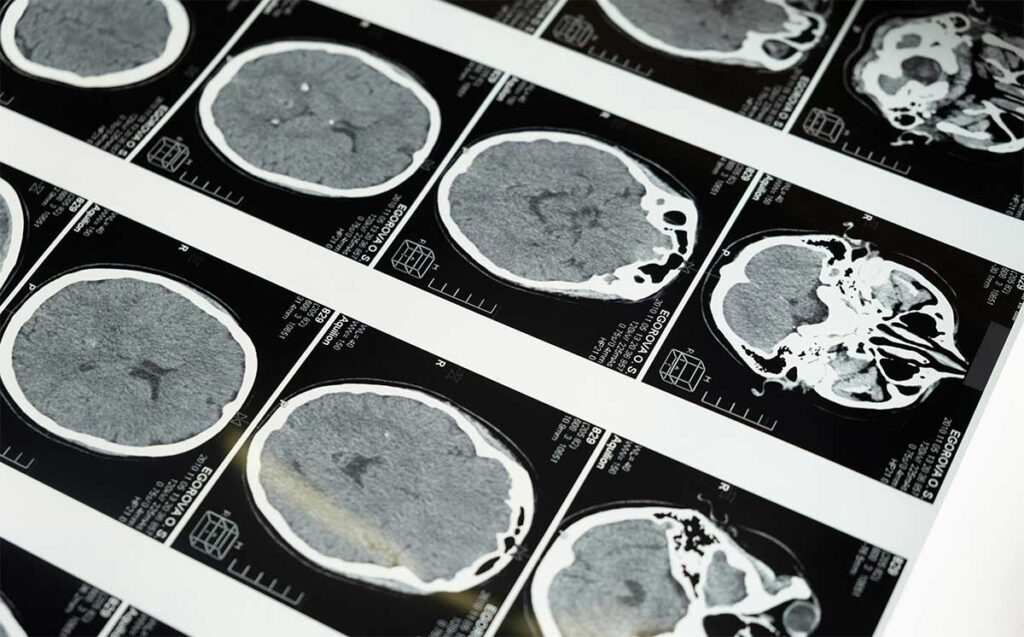

El estudio incluyó a 793 personas con una edad media de 39 años que no padecían demencia. A todos los participantes se les midió el nivel de vitamina D en sangre al inicio del estudio. Aproximadamente 16 años después, se les realizaron escáneres cerebrales para medir los niveles de las proteínas tau y beta amiloide en el cerebro, ambos biomarcadores de la enfermedad de Alzheimer.